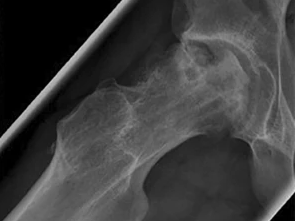

Komplikationen nach dynamischer In-situ-Fixierung des Femurkopfes bei Patienten mit Epiphyseolysis capitis femoris

Epiphyseolysis capitis femoris (ECF) ist eine nichttraumatische Epiphysenlösung in der Schenkelhalsepiphysenfuge mit Dislokation des Femurkopfes, in der Regel nach medial und dorsal während des pubertären Wachstumsschubes.

Bildnachweise

Lagerungsplagiozephalus/© Aus Linz et al. Positional Skull Deformities Etiology, Prevention, Diagnosis, andTreatment, mit freundlicher Genehmigung © Deutscher Arzte-Verlag GmbH, Röntgen eines Ellenbogens mit Humerusfraktur/© Sampaio E et al. / all rights reserved Springer Medizin Verlag GmbH, Hüftkopfnekrose eines 13-Jährigen /© Loose O et al. / all rights reserved Springer Medizin Verlag GmbH, Röntgen einer Beckenfraktur und Abdomen-CT bei Jugendlichem/© Karvouniaris N. et al. / all rights reserved Springer Medizin Verlag GmbH, Ausgeprägte fluktuierende okzipitale Schwellung am Kopf eines Babys nach Geburtstrauma/© Härtel C et al. / all rights reserved Springer Medizin Verlag GmbH, Rückenuntersuchung bei kleinem Mädchen/© Viacheslav Lakobchuk / stock.adobe.com (Symbolbild mit Fotomodellen), Schreiendes Baby/© AzmanL / Getty Images / iStock (Symbolbild mit Fotomodell), Gebrochener Arm eines Kindes erhält Gips/© Rafael Ben-Ari / stock.adobe.com (Symbolbild mit Fotomodellen), Kind mit Unterarmfraktur/© DragonImages / stock.adobe.com (Symbolbild mit Fotomodellen), Kind mit Gipsarm/© nycshooter / Getty Images / iStock (Symbolbild mit Fotomodell), Antikörper - Molekül /© luismmolina / Getty Images / iStock (Symbolbild), Adoleszente idiopathische Skoliose/© Springer Medizin Verlag GmbH, Hämatom an der Stirn des 9-Jährigen/© Dr. med. Thomas Hoppen, Morbus Perthes rechts bei 5-jährigem Jungen/© Gemeinschaftsklinikum Mittelrhein, Operative Behandlung des Torticollis muscularis congenitus/© Ploeger M et al. / all rights reserved Springer Medizin Verlag GmbH, Morbus Osgood-Schlatter/© Springer Medizin, Search Icon, Arthropedia, Frau unkenntlich fasst sich ans Knie/© Pornpak Khunatorn / Getty Images / iStock (Symbolbild mit Fotomodell), Ärzteteam führt Hüftoperation durch/© ATRPhoto / stock.adobe.com (Symbolbild mit Fotomodell), Gebrochener Fuß im Gips/© Aleksandr Kirillov / stock.adobe.com (Symbolbild mit Fotomodell)